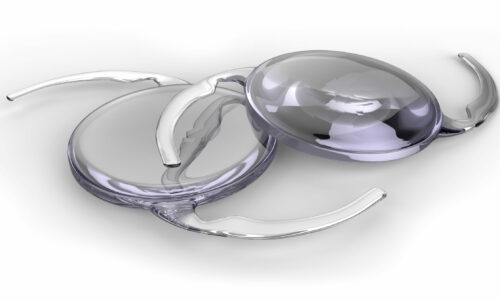

Les Implants Intraoculaires, choix et techniques de pose Plus d'info...

Les Implants Intraoculaires, choix et techniques de pose

10

857

students

280.00€139.00€